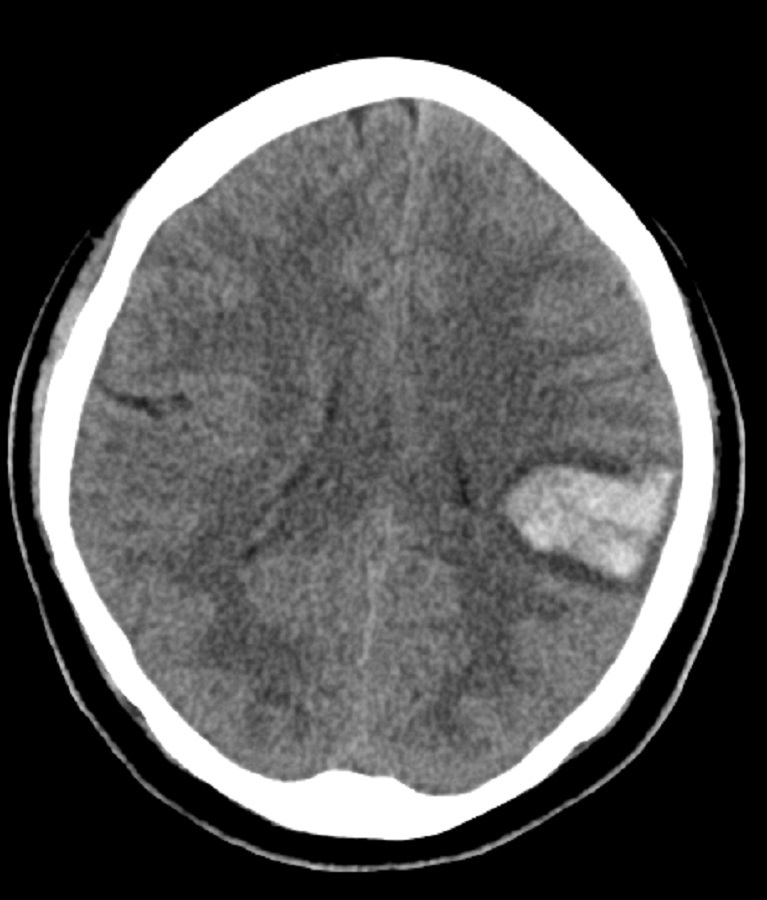

Pct com sinal neurológico focal é submetido a TC com o seguinte achado, qual o dx?

AVEh intraparenquimatoso